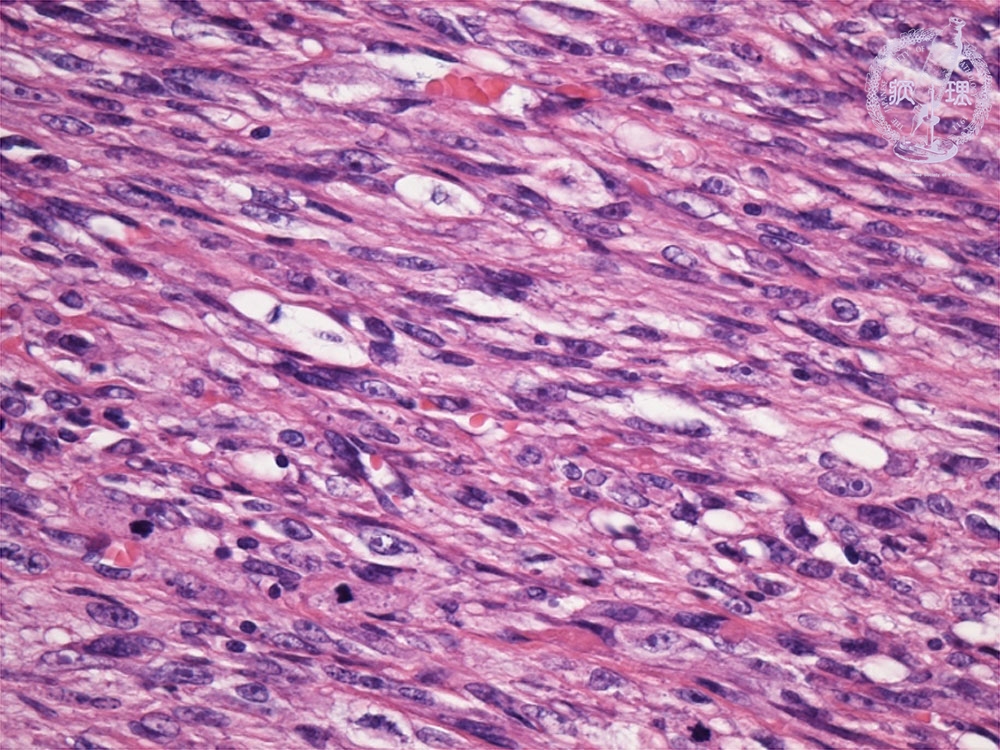

- ★(3)leiomyosarcoma

Histology (HE stain, high power): Higher nuclear density, larger nuclei, more irregular nuclei and mitotic figures compared to leiomyoma,